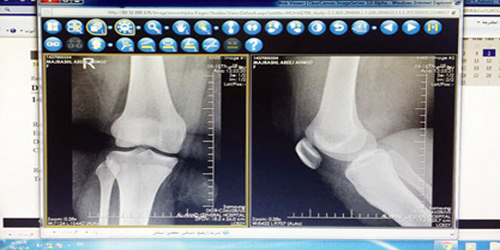

قالت وزارة الصحة إن إدارة خدمات الأشعة بصحة جازان بدأت تفعيل نظام «أرشفة ونقل صور الأشعة إلكترونيًا «ميني باكس» بمستشفى أحد المسارحة، بحضور رؤساء الأقسام الطبية والفنية بالمستشفى، وذلك ضمن خطة صحة جازان لتطبيق هذا النظام في جميع مستشفيات المنطقة.

ويسهم تفعيل نظام العرض والأرشفة الإلكترونية لصور الأشعة المعروف باسم «باكس» في سرعة عمل وتشخيص وعرض صور الأشعة، بدلاً من طريقة التخزين القديمة للصور بنظام الأرشفة اليدوية، مما قد يعرضها للضياع أو التلف مع مرور الزمن.

كما يتيح برنامج الأرشفة الإلكترونية لصور الأشعة للأطباء تصفح جميع صور فحوصات الأشعة إلكترونيًا وذلك من خلال أجهزة الكمبيوتر التي يشملها النظام الإلكتروني بالمستشفى، والاحتفاظ بكافة صور الأشعة لسنوات طويلة قادمة، والحصول عليها عند الحاجة في أي وقت وبسرعة، إلى جانب توفير طباعة أكثر من 45 ألف فيلم سنويًا.